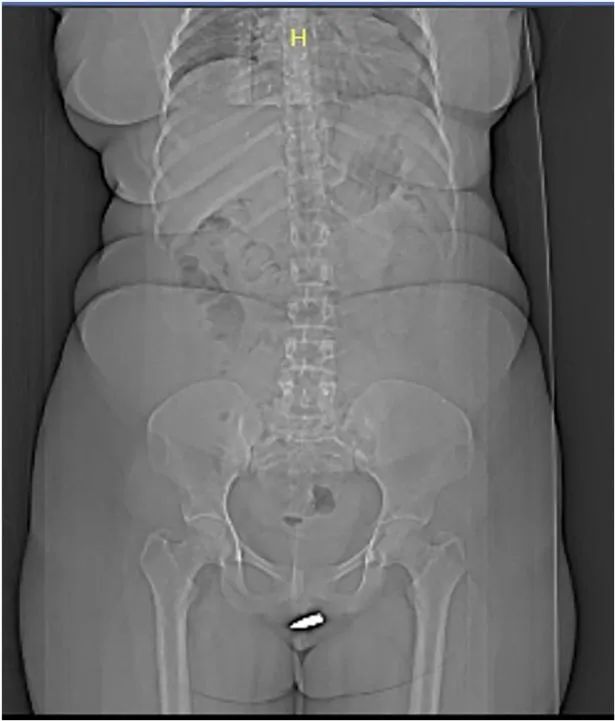

随后她被紧急送往摩加迪沙的埃尔多安医院,*弹子**被证实卡在她的阴部。在手术过程中,医生给她的*体下**进行了局部麻醉,取出了这颗讨厌的*弹子**。据医生判断,*弹子**是以低速击中她的,如果不是这种情况,她可能会有更严重的问题。手术进行得很顺利,第二天她出院时状况良好。在一个月后的随访中,一切都很正常。

她的不幸遭遇被记录在《国际外科病例报告》杂志上。文章中写道:“据我们所知,这是第一次有*弹子**穿透外阴区域,并且卡在阴蒂内。由于之前并没有记录过这样的伤害,所以我们认为这是罕见和有趣的。疲劳*弹子**伤是由低速伤害造成的,这在索马里等饱受战争*躏蹂**的国家的居民区十分常见。”